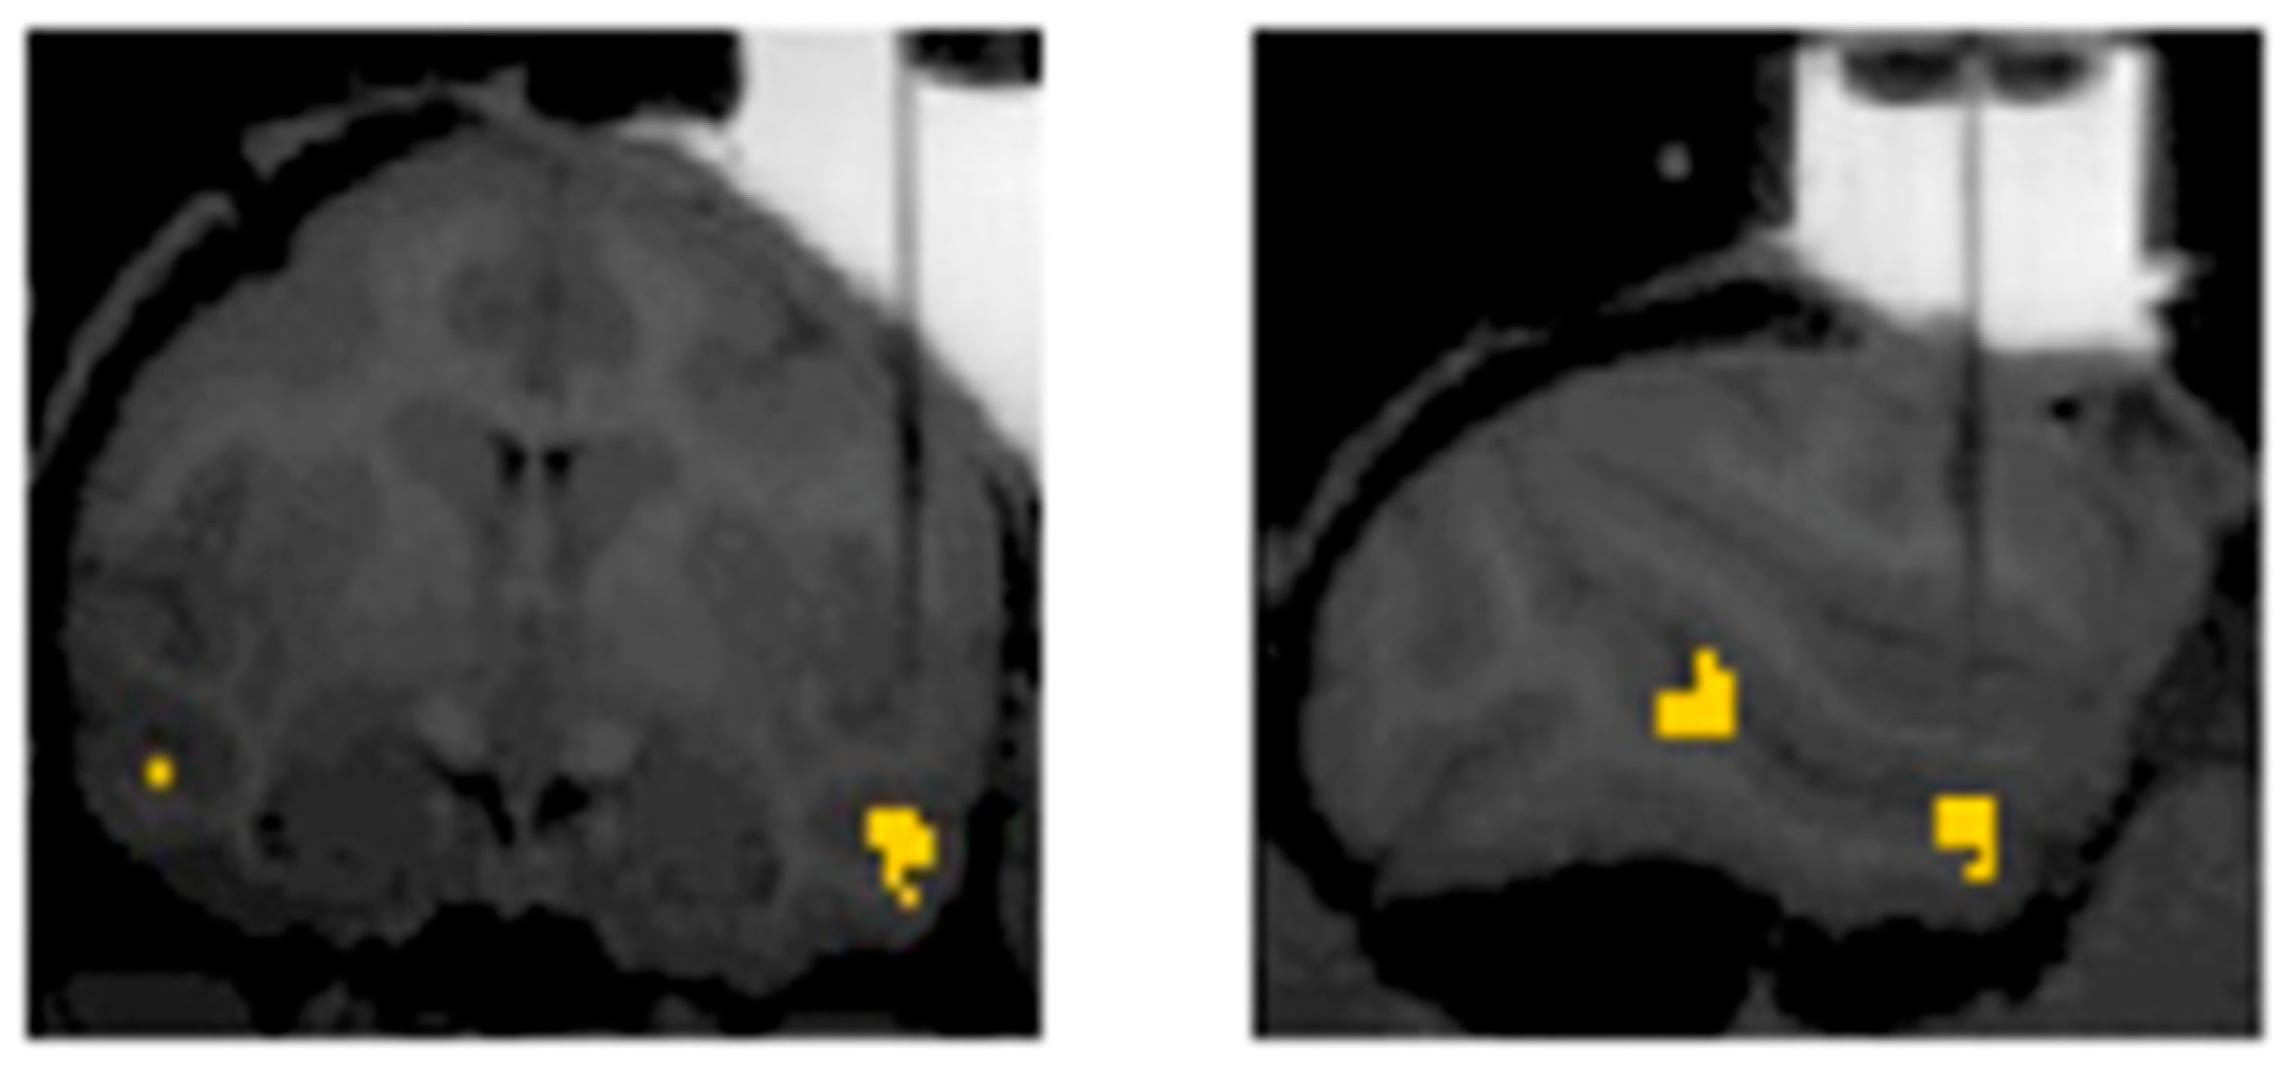

4. The Future: Clinical and Basic Neuroscience Implications